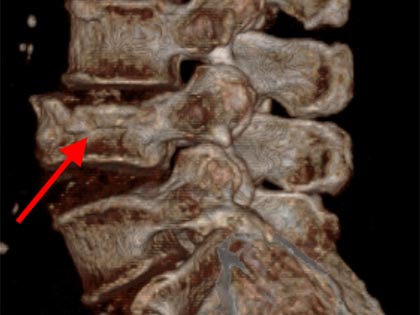

Schmerzsyndrome der Wirbelsäule; Bandscheibenvorfall; Verschleiß der Bandscheiben; Spinalkanalstenose (Verengung des Wirbelkanals); Instabilitäten; Spondylolisthesis (Wirbelgleiten), Myelopathie (Schädigung des Rückenmarkes); Querschnittslähmung; Erkrankungen bei Kinder und Heranwachsenden (z. B. Formveränderungen, Skoliosen, Kyphosen, angeborene Wachstumsstörungen, Verletzungen, Entzündungen, Tumore und Metastasen); Verletzungen des Rückenmarks; Wirbelkörperbrüche; Deformitäten (Formveränderungen, Skoliose, Kyphose); Tumore und Metastasen; Infektionen; Spondylodiszitis (Infektion von Bandscheiben und Wirbelkörper); rheumatische Instabilitäten der Halswirbelsäule sowie zwischen Kopf und Halswirbelsäule; rheumatische Veränderungen der Brust- und Lendenwirbelsäule (z. B. Morbus Bechterew);Verengungen des Foramen magnum; muskulärer Schiefhals; Syndrome durch die erste Rippe; Deformitäten des Thorax (z. B. Trichterbrust, Kielbrust); Erkrankungen und Verletzungen der Rippen; etc.